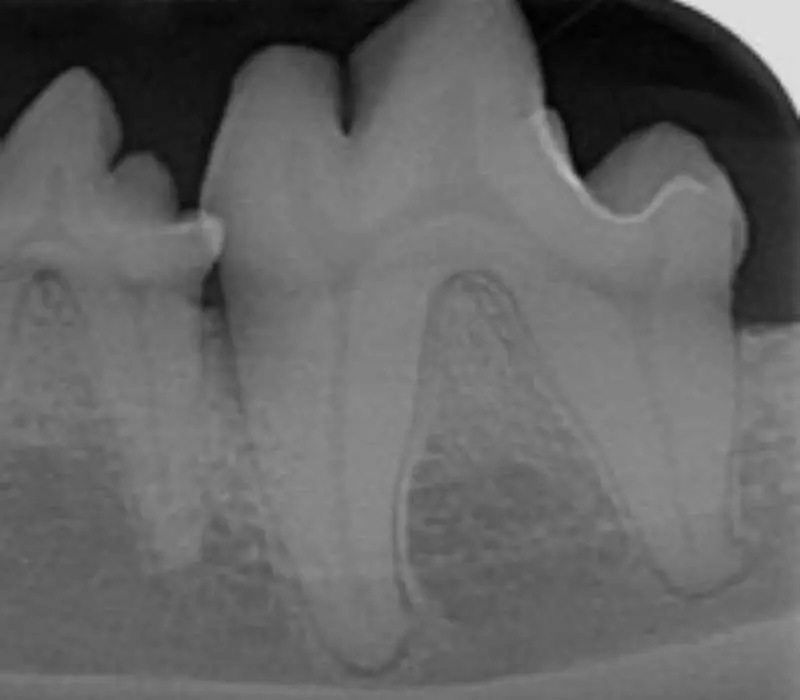

Dental radiography

- Used to identify and evaluate bone loss, identify periapical pathology and assist in treatment planning. It also helps veterinarians determine if any areas of concern require closer monitoring or more aggressive treatment.

- Monitoring progress. X-rays are helpful for tracking the progress of periodontal disease over time. Follow-up radiographs can show whether the disease is progressing or if the treatment (such as ultrasonic scaling, root planing, guided tissue regeneration or tooth extractions) has been effective (Figure 8).